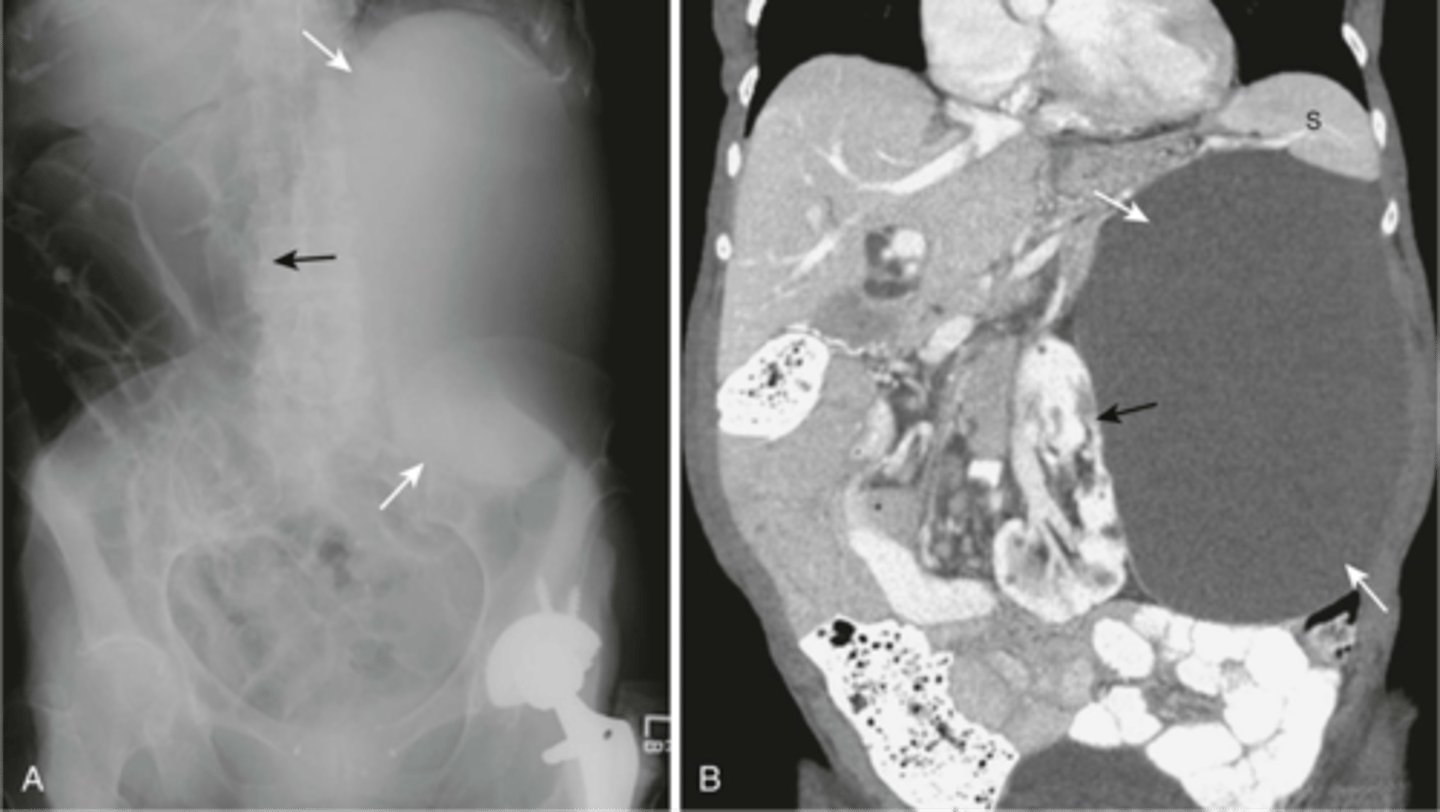

What view is this image in?

Left lateral decubitus

free air

free air under the diaphragm (indicative of pneumoperitoneum)